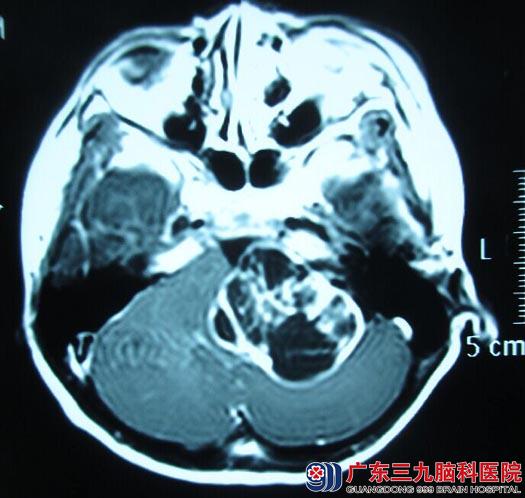

转诊到广东三九脑科医院综合神经外科,行头颅MR检查显示:左侧桥小脑角区占位性病变,大小约51mm×43mm×55mm,脑干、左侧桥壁及左侧小脑半球明显受压,考虑听神经瘤可能。